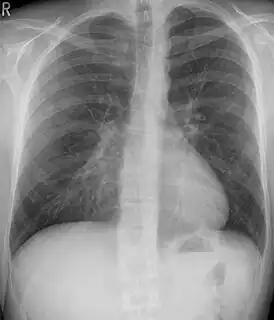

Chest x-rays are also useful in the diagnosis. The chest x-ray in pectus excavatum can show an opacity in the right lung area that can be mistaken for an infiltrate (such as that seen with pneumonia).[22] Some studies also suggest that the Haller index can be calculated based on chest x-ray as opposed to CT scanning in individuals who have no limitation in their function.[23]

Pectus excavatum on PA chest radiograph with shift of heart shadow to the left and radioopacity of the right paracardiac lung field